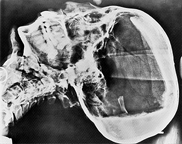

Röntgenkép Tutankhamun fáraó fejéről. Mai korban különös ez a koponyaforma.

Torzított hun koponya. Vajon miért, és hogyan készítették?..